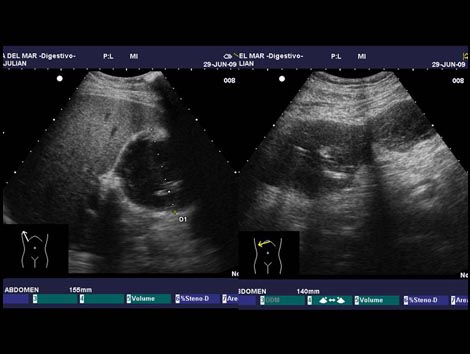

Hematoma postcolecistectomia con morfología bilobulada Dra. Paloma Rendón |

Hematoma tras colecistectomia laparoscópica Dra. Paloma Rendón |